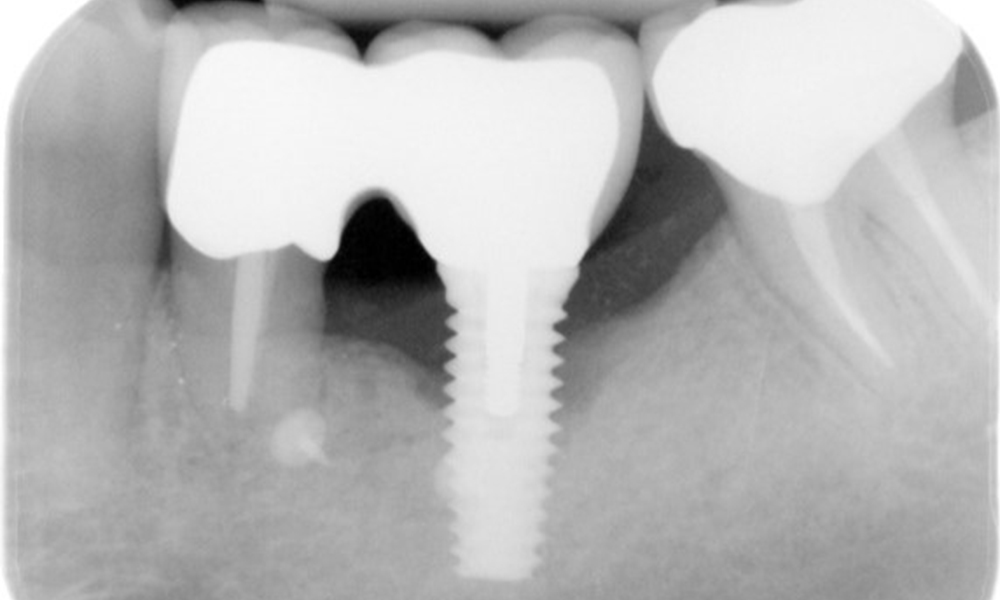

The X-ray images show the progression of bone loss in the area of the implant in region 36: dental film from 11.02.2021 (left) and dental film from 18.01.2024 (right).

OPG: 26/02/2024 Dental X-ray: 18/01/2024